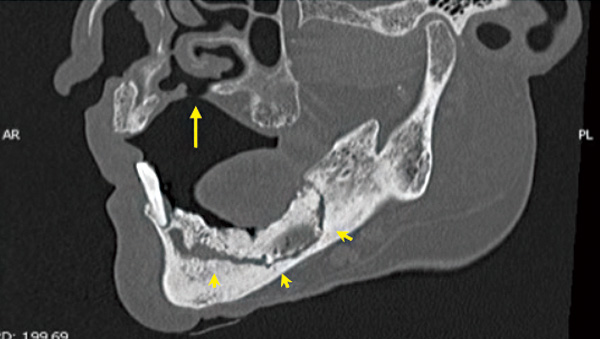

下顎前歯と左下に骨露出あり。

CTでは広範囲の鼻腔と交通する瘻孔(矢印)と下顎下縁に至る腐骨形成(矢印)が確認されます。